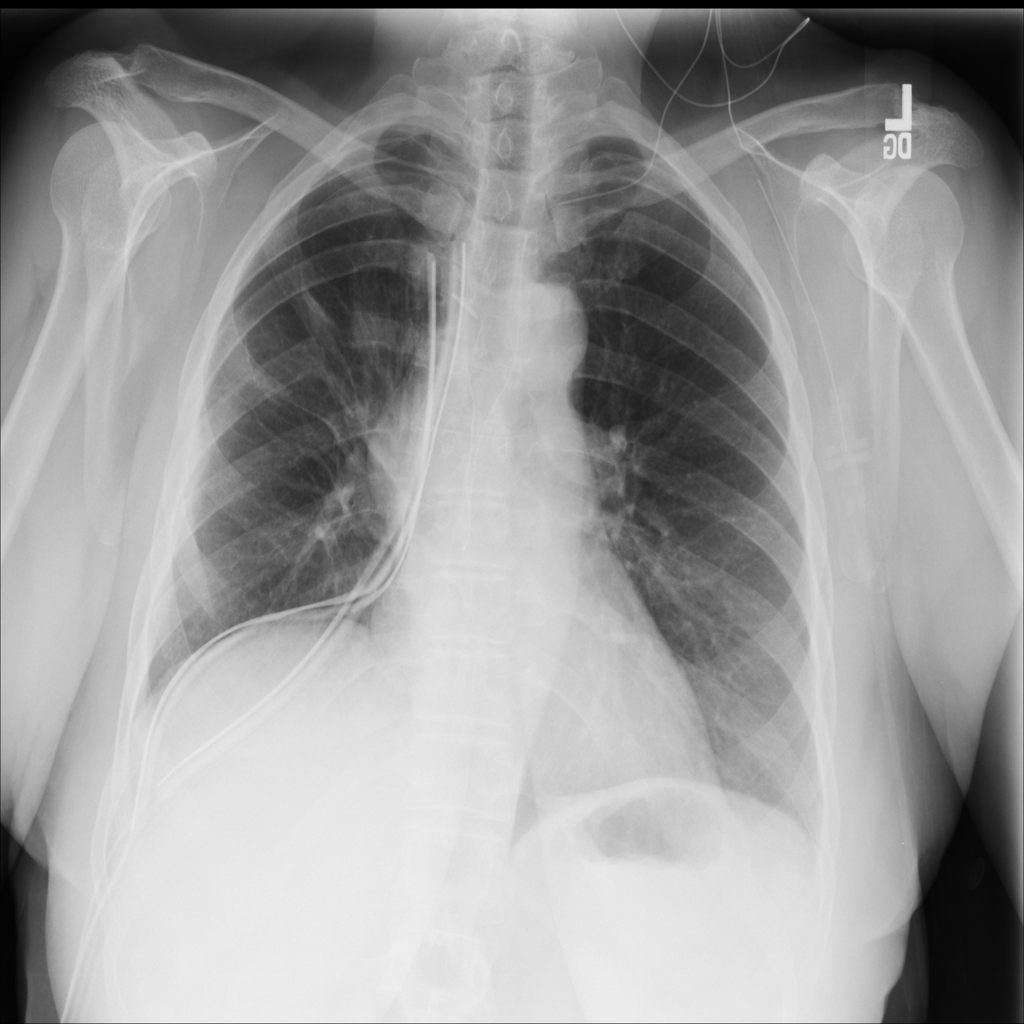

Pneumothorax

Pneumothorax means air is present outside the lung in the pleural space, which can allow part of the lung to collapse. It is an important imaging finding because the size and clinical impact can vary widely.

Showing up to 90 reference images for Pneumothorax.

PAT-4114 · IMG-008Pneumothorax

PAT-4114 · IMG-008

PA